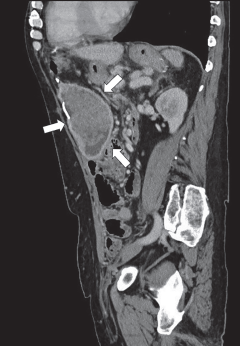

Figura 1 Tomografía de abdomen simple en plano axial